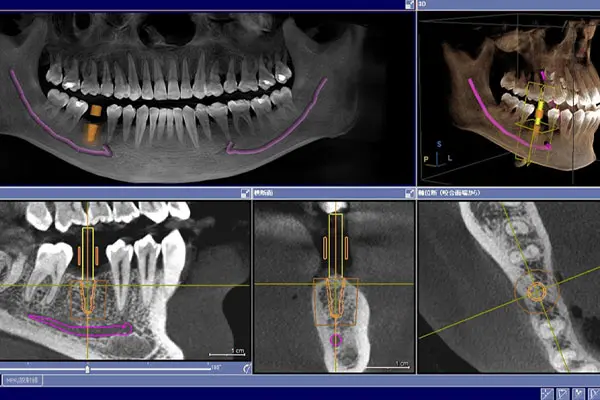

実際にインプラントが入っている方のCT画像を見ると、

- 被せ物(銀歯など)からは強いアーチファクトが出る

- インプラント体そのものからは、ほとんどアーチファクトが出ない

というケースがほとんどです。

👉 つまり、CT検査においてインプラントはほぼ問題にならないということです。